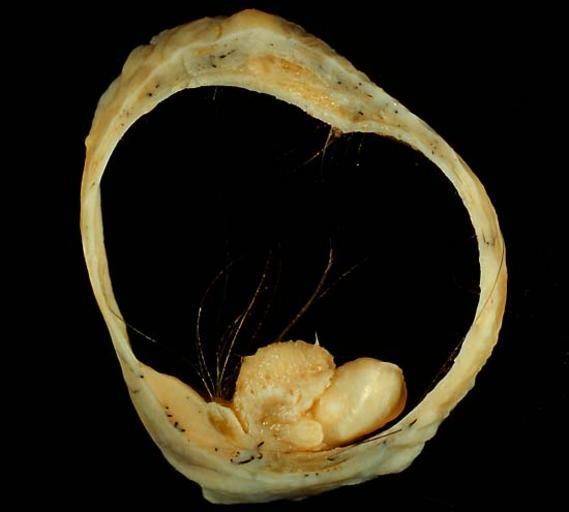

MAKE A MEME View Large Image Mature cystic teratoma of ovary 2.jpg This is the same case presented in Image Mature cystic teratoma of ovary jpg The photo shows a well-developed tooth arising from the right side of the mural nodule Rokitansky nodule that contains most ...

Keywords: Mature cystic teratoma of ovary 2.jpg This is the same case presented in Image Mature cystic teratoma of ovary jpg The photo shows a well-developed tooth arising from the right side of the mural nodule Rokitansky nodule that contains most of the solid teratomatous elements The central portion of the nodule contains mostly cutaneous tissues skin sweat glands and hair follicles while the neural tissues extend into the wall toward the left In the past the teratoma literally monster tumor was considered to be a conceptus and according to an ancient Merck Manual I remember reading the Roman Catholic Church required that teratomas be baptized Currently neither pathologists nor the Vatican considers teratomas to be anything other than germ cell tumors of host origin only with no paternal contribution These photos were shot on Ektachrome Elite 100 film daylight type through a blue filter to correct the emission spectrum of the Photofloods used on the copy stand The exposure was f/8 for 1/4 second using a Minolta X-370 fitted with bellows The key to a good photo of a teratoma is to clean out all the greasy material in the cyst To do this on receipt of the specimen I palpated the external surface to determine where the mural nodule was Then at the antipodes of the nodule I carefully made a straight gentle incision that extended for about half the circumference of the specimen I did not express the contents not distort the cyst in any way Then I soaked the specimen in Carnoys' fluid overnight By the next day the grease had been broken up and diluted enough that I could gently wash it out of the lumen with more Carnoy's This left a squeaky-clean internal surface and all I had to do was extend my original incision all the way around the specimen using scissors for the thin part of the wall Photograph by Ed Uthman MD Public domain Posted 27 May 01 http //web2 airmail net/uthman/specimens/index html PD Ed Uthman Gross pathology of neoplasms Gross pathology of teratoma Photographs taken on Ektachrome and Elite Chrome film